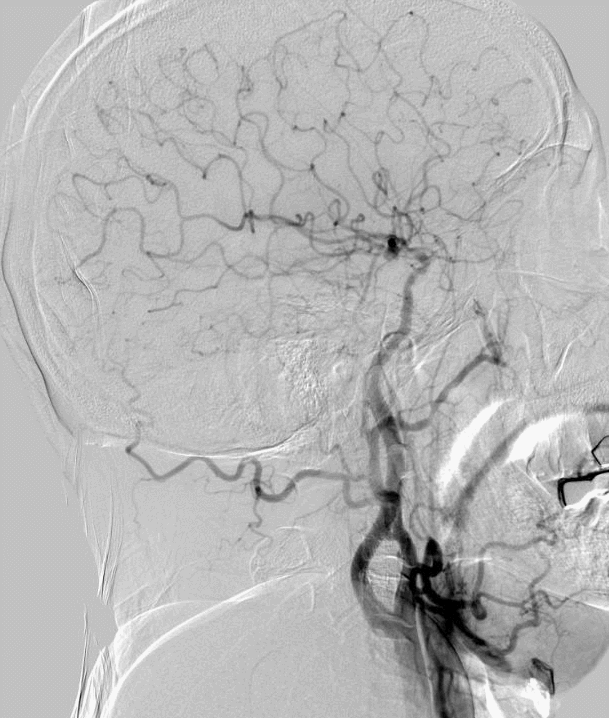

术前DSA

15min后,观察正侧位、3D旋转,可见狭窄较前明显改善。

什么叫桡鞘【例久弥新】寻道于桡——瑞康通5.5F Introsky X导管鞘经桡取栓一例_https://www.jmylbn.com_新闻资讯_第25张

什么叫桡鞘【例久弥新】寻道于桡——瑞康通5.5F Introsky X导管鞘经桡取栓一例_https://www.jmylbn.com_新闻资讯_第26张

什么叫桡鞘【例久弥新】寻道于桡——瑞康通5.5F Introsky X导管鞘经桡取栓一例_https://www.jmylbn.com_新闻资讯_第27张